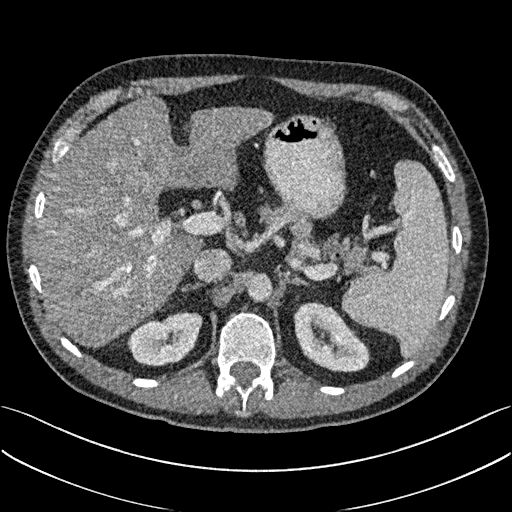

To show the denoising effect of the selected networks, we took two representative slices as shown in Figs. 5 and 7. And Figs. 6 and 8 are the zoomed regions-of-interest (ROIs) marked by the red rectangles in Figs. 5 and 7. All the networks demonstrated certain denoising capabilities. However, CNN-MSE blurred the images and introduced waxy artifacts as expected, which are easily observed in the zoomed ROIs in Figs. 6e and 8e. WGAN-MSE was able to improve the result of CNN-MSE by avoiding over-smooth but minor streak artifacts can still be observed especially compared to CNN-VGG and WGAN-VGG. Meanwhile, using WGAN or GAN alone generated stronger noise (Figs. 6g and 8g) than the other networks enhanced a few white structures in the WGAN/GAN generated images, which are originated from the low dose streak artifact in LDCT images, while on the contrary the CNN-VGG and WGAN-VGG images are visually more similar to the NDCT images. This is because the VGG loss used in CNN-VGG and WGAN-VGG is computed in a feature space that is trained previously on a very large natural image dataset [48]. By using VGG loss, we transferred the knowledge of human perception that is embedded in VGG network to CT image quality evaluation. The performance of using WGAN or GAN alone is not acceptable because it only maps the data distribution from LDCT to NDCT but does not guarantee the image content correspondence. As for the lesion detection in these two slices, all the networks enhance the lesion visibility compared to the original noisy low dose FBP images as noise is reduced by the different approaches.

As for iterative reconstruction technique, the reconstruction results depend greatly on the choices of the regularization parameters. The implemented dictionary learning reconstruction (DictRecon) result gave the most aggressive noise reduction effect compared to the network outputs as a result of strong regularization. However, it over-smoothed some fine structures. For example, in Fig. 8, the vessel pointed by the green arrow was smeared out while it is easily identifiable in NDCT as well as WGAN-VGG images. Yet, as an iterative reconstruction method, DictRecon has its advantage over post-processing method. As pointed by the red arrow in Fig 8, there is a bright spot which can be seen in DictRecon and NDCT images, but is not observable in LDCT and network processed images. Since the WGAN-VGG image is generated from LDCT image, in which this bright spot is not easily observed, it is reasonable that we do not see the bright spot in the images processed by neural networks. In other words, we do not want the network to generate structure that does not exist in the original images. In short, the proposed WGAN-VGG network is a post-processing method and information that is lost during the FBP reconstruction cannot easily be recovered, which is one limitation for all the post-processing methods. On the other hand, as an iterative reconstruction method, DictRecon algorithm generates images from raw data, which has more information than the post-processing methods.